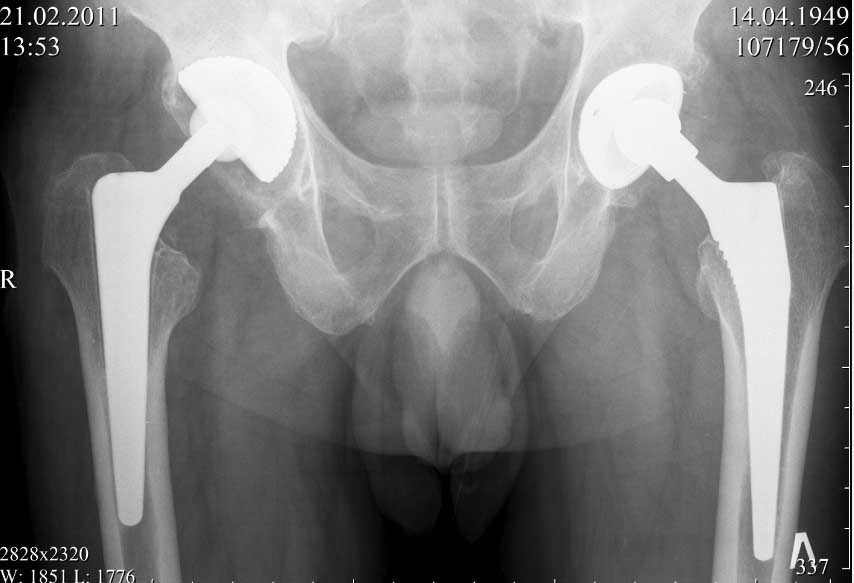

ниже снимок в 2008 году

далее снимок в 2009 году

далее снимок у меня на приеме

Пациент 60 лет, мужчина. Оперирован в 2007 году, поочередно оперированы два тазобедренных сустава с интервалом в 4 месяца. В 2008 году оперирован на сердце(аорто-коронарное шунтирование).Операция осложнилась инфицированием операционной раны в области грудины, лечился в гнойном отделении.

В конце 2008 года отметил боли в правой паховой области при опоре на правую ногу. На рентген снимках таза с тазобедренными суставами явных признаков нестабильности вертлужного компонента не обнаружено. В 2009 году нейрохирурги его "успешно" прооперировали на L\3-\4 связывая болевой синдром в правой паховой области с наличием грыжи указанного межпозвонкового диска. Состояние только ухудшилось, больной уже не мог долго сидеть, боль прогрессировала . Его в 2009 и 2010 годах смотрел ортопед, делались рентгенснимки, но почему то приходили к выводу что эндопротез справа стабилен. В марте 2011 года я впервые увидел его, через одну неделю после этого был прооперирован. На операции вертлужный компонент при упоре на него инструментом прокручивался во впадине и без труда был извлечен.

Эндопротез Ножка Cerafit компании Ceraver- чашка той же компании.

Расшорошили вертлужную впадину (дебридмент) Заменили чашку,учитывая невозможность полностью исключить инфекционный генез нестабильности, установили вертлужный компонент цементной фиксации (цемент с ванкомицином), поменяли головку из-за изменившихся взаимоотношении между бедренным компонентом и новой чашкой. Рану зашили наглухо. Провели антибактериальную терапию Кубицином. Выписали на 10 сутки после операции. Болевой синдром купирован, пациент радостный, уехал к себе в Калугу. Приедет на контрольный осмотр через месяц.

при этом, у этого пациента была СОЭ 20 мм в час, лейкоциты и формула лейкоцитарная в норме. Можно было пунктировать сустав, но мы этого не сделали и оказались правы: при вскрытии сустава на операции, сустав был сухой и жидкость для посева мы бы не получили.

Но все же, мы провели его лечение как инфицированного, учитывая анамнез: нагноение операционной раны грудины, после операции на сердце. К тому, боли в правом тазобедренном суставе он отметил после осложненной операции на сердце.

На заключительных снимках явная нестабильность чашки и вероятная ножки, возможно на повторный прием придет не столь радостный (пессимистический прогноз) надеюсь, что все будет по-другому

Нет вы не поняли! Вы поспешили с выводом! Я не смог выслать окончательный, послеоперационный снимок, по техническим причинам. Я это сделал позже, что Вы и видите ниже! Извините, если я Вас запутал!

С последним, третьим снимком он ко мне и обратился, после чего он был и прооперирован на правом тазобедренном суставе!

В дополнение к моему вышеуказанному пациенту. Досылаю послеоперационный снимок, который я не выслал сразу.